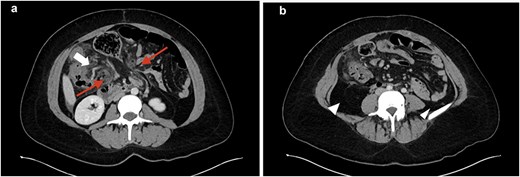

A 35-year-old female presented with acute abdominal pain, nausea, and vomiting. She reported a similar episode one week earlier that resolved without further symptoms. Comorbidities included obesity, lupus, and celiac disease, and she had recently started tirzepitide. Her only prior intra-abdominal surgery was a laparoscopic ovarian dermoid tumor removal. Her abdomen was minimally distended and tender over the left hemiabdomen without peritonitis. Abdominal computed tomography (CT) scan showed distended small and large bowel, mesenteric swirling, pericolonic fat stranding, and medial displacement of both the ascending and descending colon (Fig. 1a and b). With these findings and her ongoing symptoms, urgent exploratory laparotomy was performed. Intraoperatively, the omentum was noted to be thin with multiple defects. The distal omentum was necrotic, wrapped around the base of the mesentery (Fig. 2a and b). All bowel was viable. A Meckel’s diverticulum was identified, measuring approximately 2 cm at the base. A stapled Meckel’s diverticulectomy was performed. Both the ascending and descending colon were freely mobile, lacking lateral attachments. A necrotic epiploic appendage was also resected (Fig. 2c). An appendectomy was also performed. Her postoperative course was uneventful, and she was discharged on postoperative day 3. On pathology, the resected omentum was found to be a hemorrhagic omentum with fibrous adhesions, the Meckel’s diverticulum contained gastric mucosa, and the appendix was normal. At her 4-week follow-up, she continued to recover well.

CT images. a: Small and large bowel (top arrow) herniating through omentum (bottom two arrows); b: Intra-abdominal fat displacing colon to the midline (arrowhead).